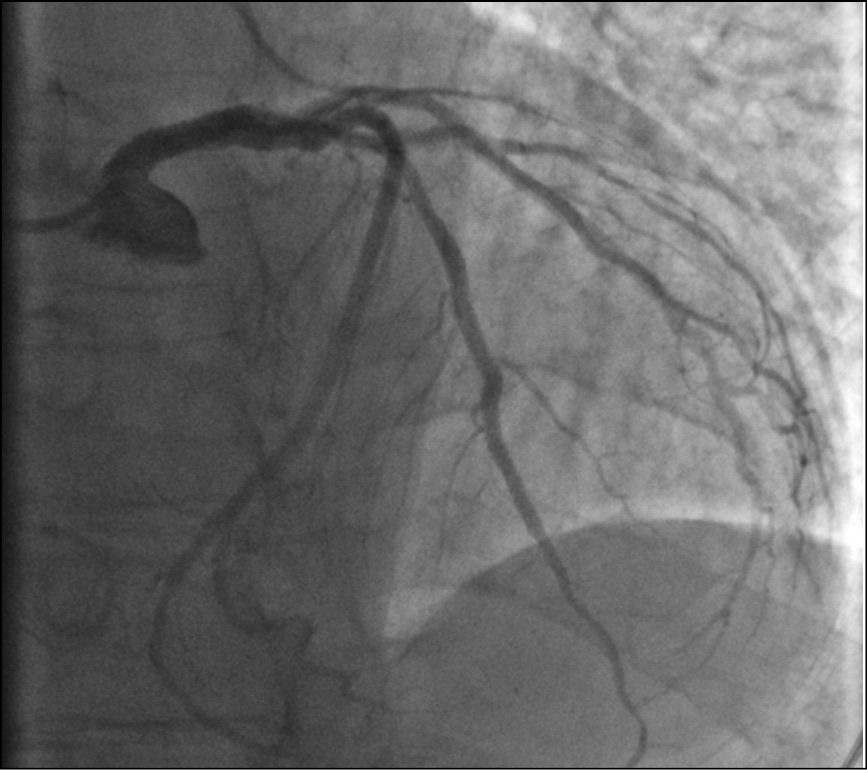

По данным селективной коронарографии визуализируется расслоение ствола левой коронарной артерии (рис. 3, a), остальной бассейн левой коронарной артерии без гемодинамически значимых поражений (рис. 3, b); правая коронарная артерия без особенностей (рис. 4). Левый тип кровоснабжения миокарда.

Рис. 3. Тот же пациент: селективная коронарография левой коронарной артерии.

Примечание. a — увеличенное изображение (расслоение ствола левой коронарной артерии отмечено стрелкой); b — передняя нисходящая, огибающая, диагональная артерии и ветвь тупого края без гемодинамически значимых поражений (стрелкой отмечено расслоение ствола левой коронарной артерии).

Fig. 3. The same patient: selective coronary angiography of the left coronary artery.

Note. a — enlarged image (dissection of the trunk of the left coronary artery is marked with an arrow); b — left anterior descending, circumflex, diagonal arteries and obtuse marginal branch without a hemodynamically significant damage (dissection of the trunk of the left coronary artery is marked with an arrow)